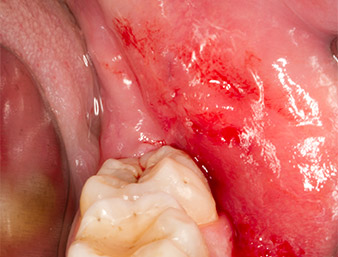

After block and local anaesthesia, the operating site was opened up and the soft tissue exposed for buccal retromolar access (Fig. 3).

sulcular incision

Fig. 3: The sulcular incision begins in mid-tooth 36 (LL6), with distal extension on the ascending ramus.

The tissue above the root remnant was not completely ossified and consisted for the most part of granulation tissue modified by inflammation (Fig. 4).